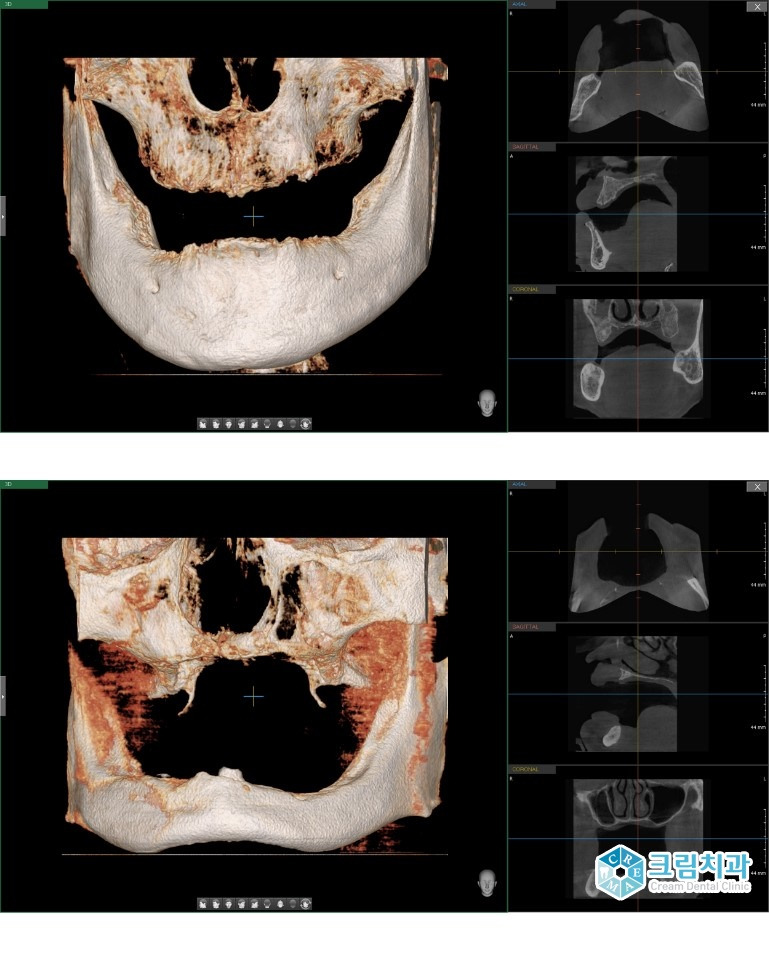

무치악의 경우 3차원 컴퓨터단층촬영(3D CT)을 통해 촬영한 사진을 비교해보면 치아(위)는 적절한 시기에 발치를 한 결과 아래턱 및 위턱 잇몸뼈가 보존이 잘 되어 임플란트 식립에 적합합니다. 그러나 치아(아래)는 만성치주염을 오랜동안 방치함으로 인해 잇몸뼈가 녹아 상당 부분 소실되어 임플란트 식립에 문제가 있을 수 있기에 전문 의료진의 검진이 필요합니다.